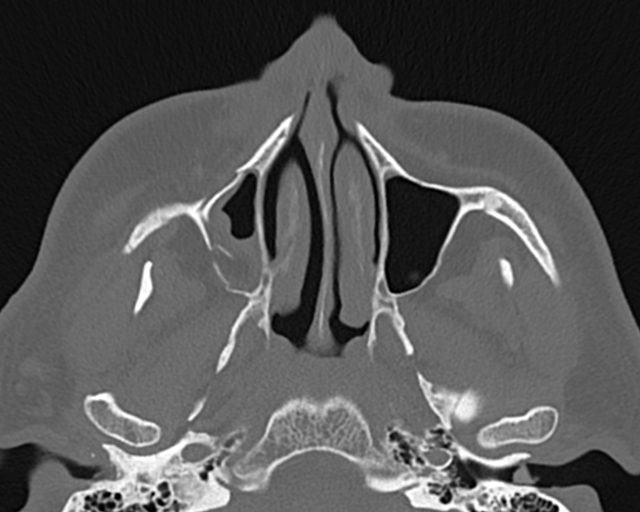

سی تی اسکن از سقف اربيت تا غضروف تيروئيد ( مقاطع تهيبدون کنتراست (مولتي ديدکتور 16 با مقاطع ظريف و بازسازي هاي ساژيتال و کرونال و 3D):

– انحراف سپتوم مياني بينی به چپ

– Fx با جابجايي خفيف در ديواره آنتريور سينوس ماگزيلاري راست با گسترش به ديواره فوقاني ( کف اربيت راست )

– FX با جابجايي در ديواره پوسترولترال اربيت راست همراه با هماتوم و دفورميتي سينوس

– Fx با جابجايي در ديواره لترال اربيت راست و گسترش به زايگوماي راست

– Fx سگمنتال با جابجايي در قوس زايگوماي راست

-retention cyst در کف سينوس ماگزيلاري چپ مشهود است .